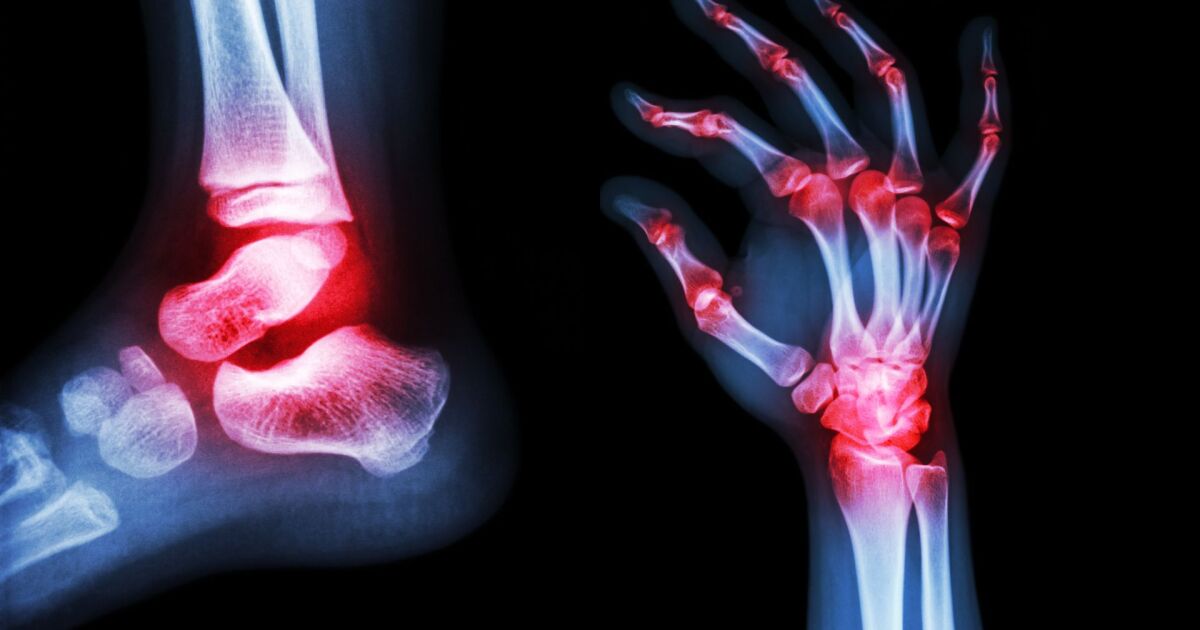

Ревматоидният артрит е автоимунно заболяване, при което имунната система атакува здравите тъкани в организма, особено синовиалната обвивка на ставите. За разлика от остеоартрита, който е свързан със застаряването, ревматоидният артрит е заболяване на имунната дисфункция.

„Това не е болест на старостта - това е болест на имунната дисфункция,“ обяснява д-р Рошел Розиан, ревматолог от Cleveland clinic. Заболяването най-често засяга малките стави на ръцете и краката, но може да повлияе на всяка става в тялото.

Ревматоидният артрит (РА) е хронично автоимунно заболяване. За разлика от остеоартрита, който е резултат от износване на хрущяла, при РА имунната система по погрешка атакува собствените си тъкани, предимно ставите. Това води до възпаление, болка, подуване и скованост.

- Образна диагностика: Рентгенография, ядрено-магнитен резонанс или ехография, които помагат да се види състоянието на ставите и да се открият увреждания.